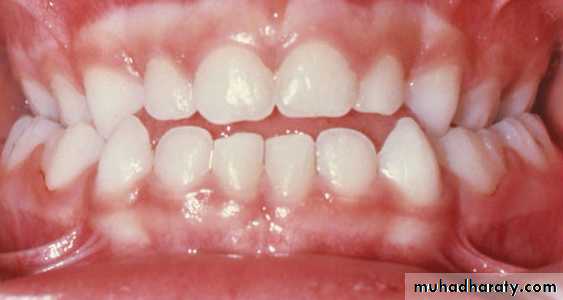

In all patients whether children or adolescents, the crossbite should be overcorrected so that the palatal cusps of upper teeth occlude on the lingual inclines of buccal cusps of lower molars.

overcorrection

The crossbite should be slightly overcorrected so that the palatal cusps of upper teeth occlude on the lingual inclines of buccal cusps of lower molars.

After retention